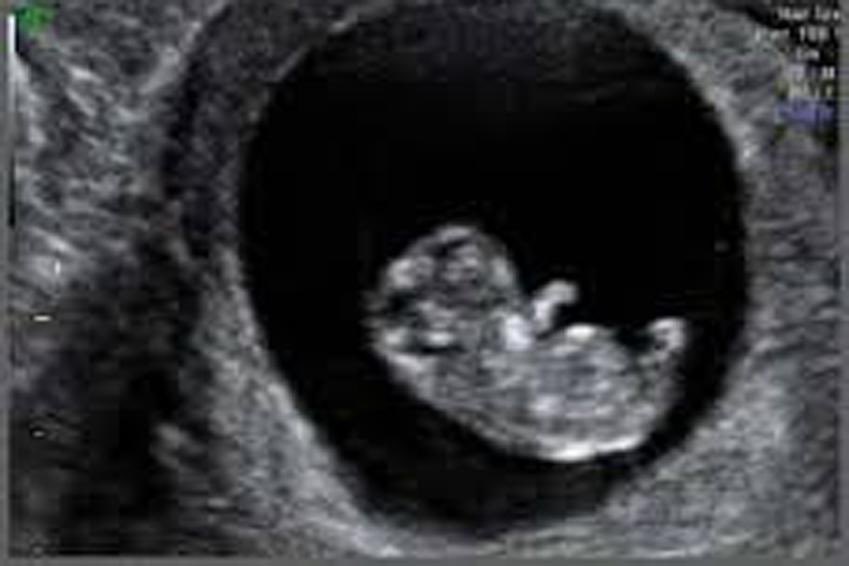

٩- بعد اسبوعين من ترجيع الاجنة يتم عمل تحليل الدم الرقمي لمعرفة حدوث الحمل واذا كان ايجابيا يتم تكراره مرتين لمعرفة ارتفاع مستواه وبعد أسبوعين من التحليل الايجابي أي ٤ أسابيع من تاريخ إرجاع الأجنة يتم عمل الاشعة الصوتية لمعرفة مكان الحمل وعدد اكياس الحمل ونبض الجنين..